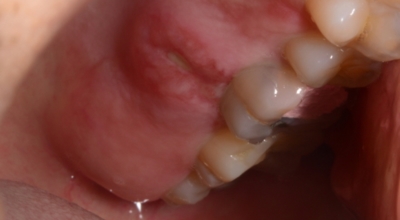

피부에 발생되는 편평 태선등의 것으로 자가면역질환의 한 가지로 알려져 있습니다. 주로 유전적인 까닭 및 면역 반응의 이상으로 나타나는 구내염으로 거미줄처럼 실선이 얽기 설기는 형태로 구내염이 발생해요. 발생 까닭이 명확하지 않아 치료가 어려우나 스테로이드 연고제를 통해 증상을 완화할 수 있습니다. 이런 형태의 구내염이 긴 시간 지속될 경우 구강암으로 발전할 수 있기 때문에 반드시 병원에서 진료를 받아봐야 해요.